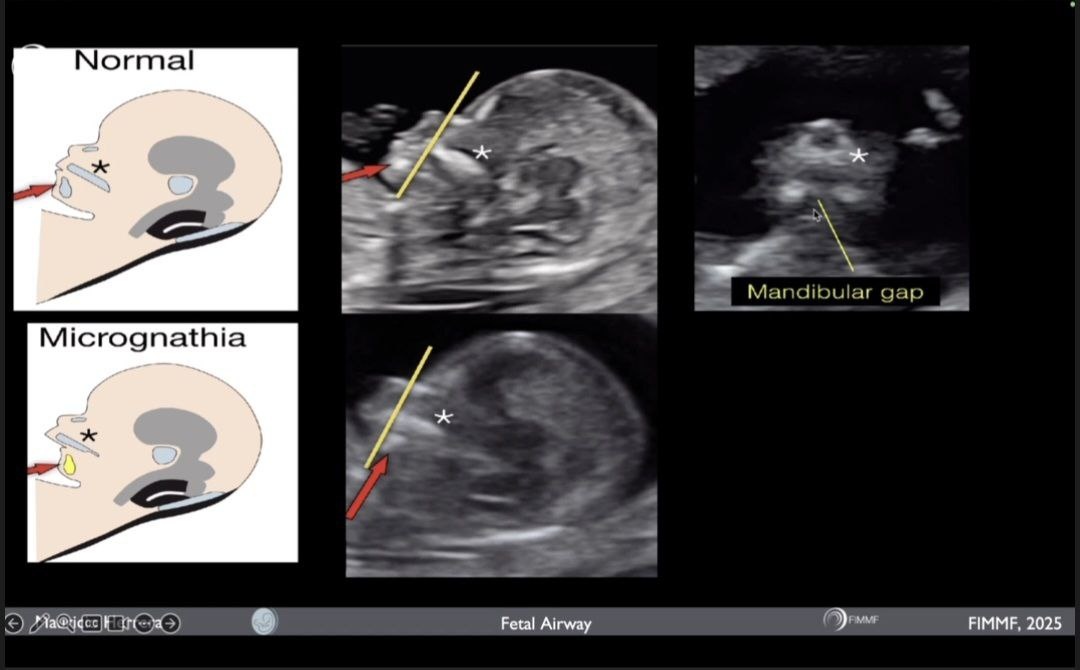

В норме подбородок, нижняя челюсть, верхняя губа и нос расположены на одной линии в срединно-сагитальном срезе. Это простая субъективная оценка.

В случае микрогнатии при оценке профиля плода возникает ощущение неправильного прикуса из-за малой и/или смещенной кзади нижней челюсти.

Для оценки размера нижней челюсти важен срединно-сагиттальный срез головы. Необходимо избегать сгибания шеи или подтягивания подбородка, что затрудняет правильную визуализацию.

Диагноз можно заподозрить в I триместре (12-14 нед) при осмотре профиля плода в срединно-сагитальном срезе и оценке ретроназального треугольника, обычно во время проведения I пренатального скрининга. Отсутствие нижнечелюстного промежутка является ранним диагностическим признаком неправильного формирования нижней челюсти.